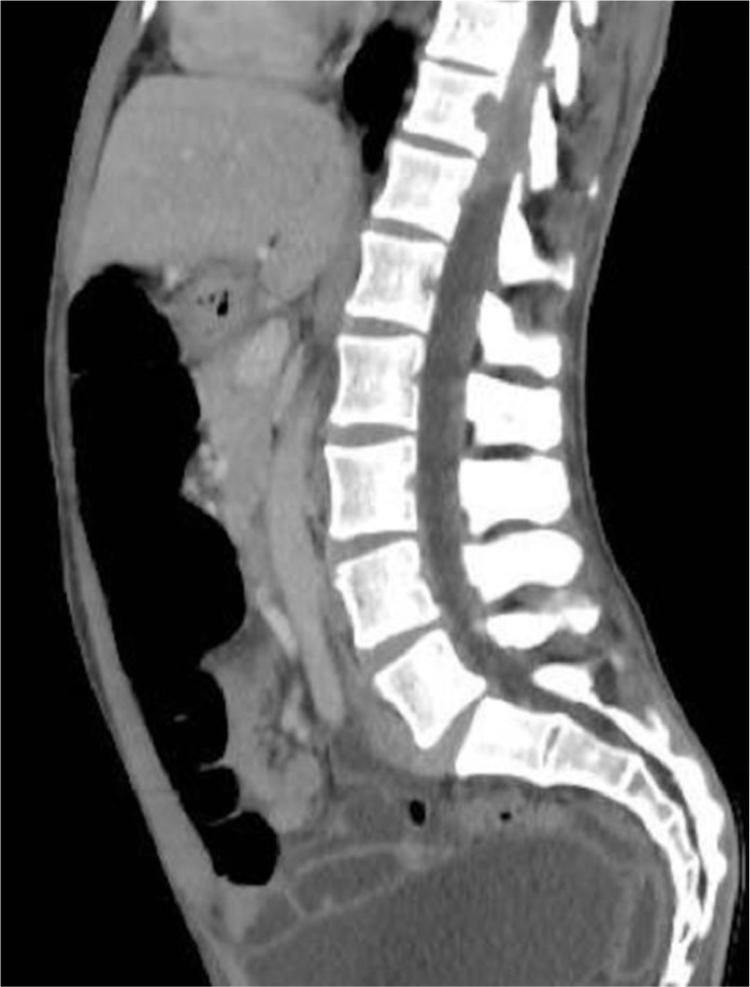

Epstein Barr virus-associated smooth muscle tumors are an uncommon neoplasm that occurs in immunosuppressed patients of any age. Usually, it presents as multifocal tumors mainly in the spinal cord, epidural region, gastrointestinal tract and liver, upper respiratory tract and skin, the latest with few cases reported in the literature and related with human immunodeficiency virus infection and acquired immune deficiency syndrome. The authors present the first case of a Colombian adult patient with human immunodeficiency virus infection and multifocal Epstein Barr virus-associated smooth muscle tumors in the skin and epidural region, confirmed by histopathology, immunohistochemistry and in situ hybridization studies.

Epstein Barr 病毒相关平滑肌肿瘤是一种罕见的肿瘤,发生于任何年龄的免疫抑制患者。通常,它表现为多灶性肿瘤,主要发生在脊髓、硬膜外区域、胃肠道和肝脏、上呼吸道和皮肤,最近文献中报道了少数与人类免疫缺陷病毒感染和获得性免疫缺陷综合征相关的病例。作者报告了首例哥伦比亚成人患者,该患者感染人类免疫缺陷病毒,皮肤和硬膜外区域有多发性 Epstein Barr 病毒相关平滑肌肿瘤,通过组织病理学、免疫组织化学和原位杂交研究得到证实。